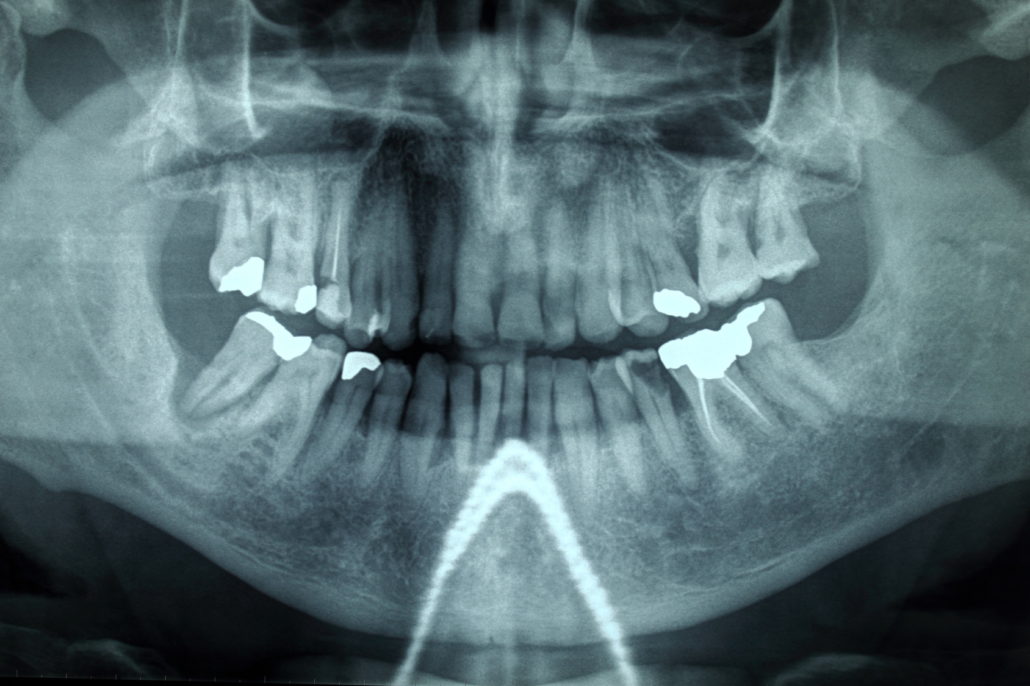

Cos’è l’Ortopantomografia?

Con il termine ortopantomografia si intende quell’esame radiografico che ci permette di vedere entrambe le arcate dentarie in una sola radiografia.

Solitamente questo esame si esegue presso studi radiologici o negli studi dentistici che possiedono l’ortopantomografo che è quel macchianario che ci permette di fare queste radiografie.